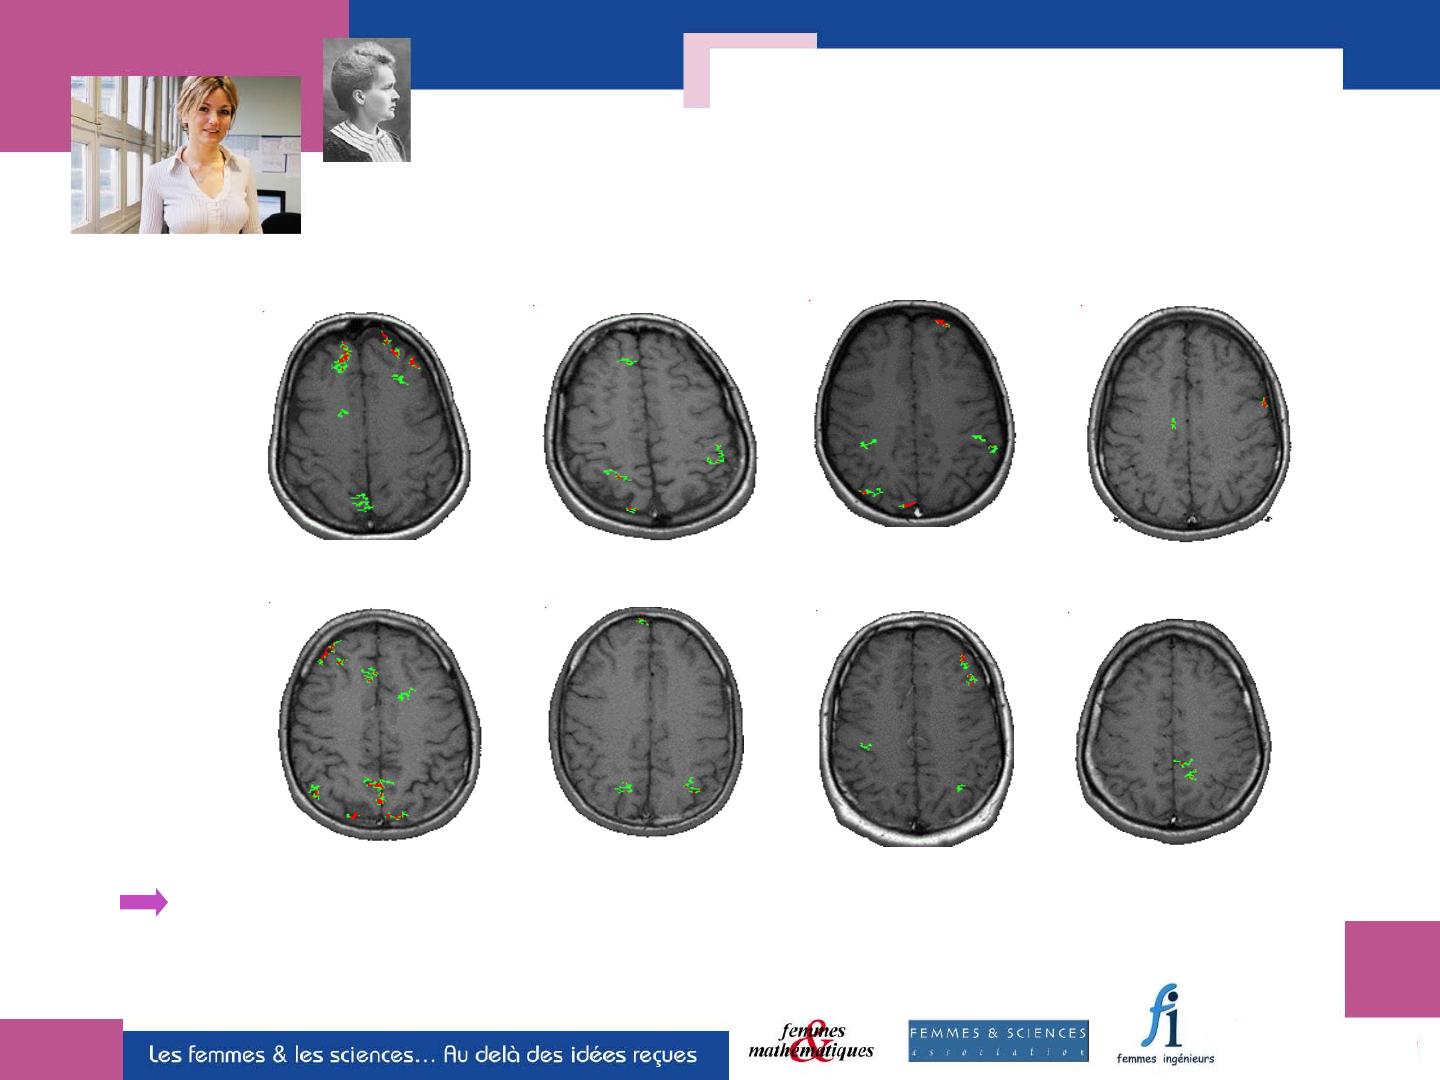

IRM du cerveau pendant un test

de calcul mental

Hommes

Femmes

Pour un même test, chaque individu a sa propre façon d’activer son cerveau

Les différences cérébrales entre les individus d’un même sexe

dépassent les différences entre les sexes